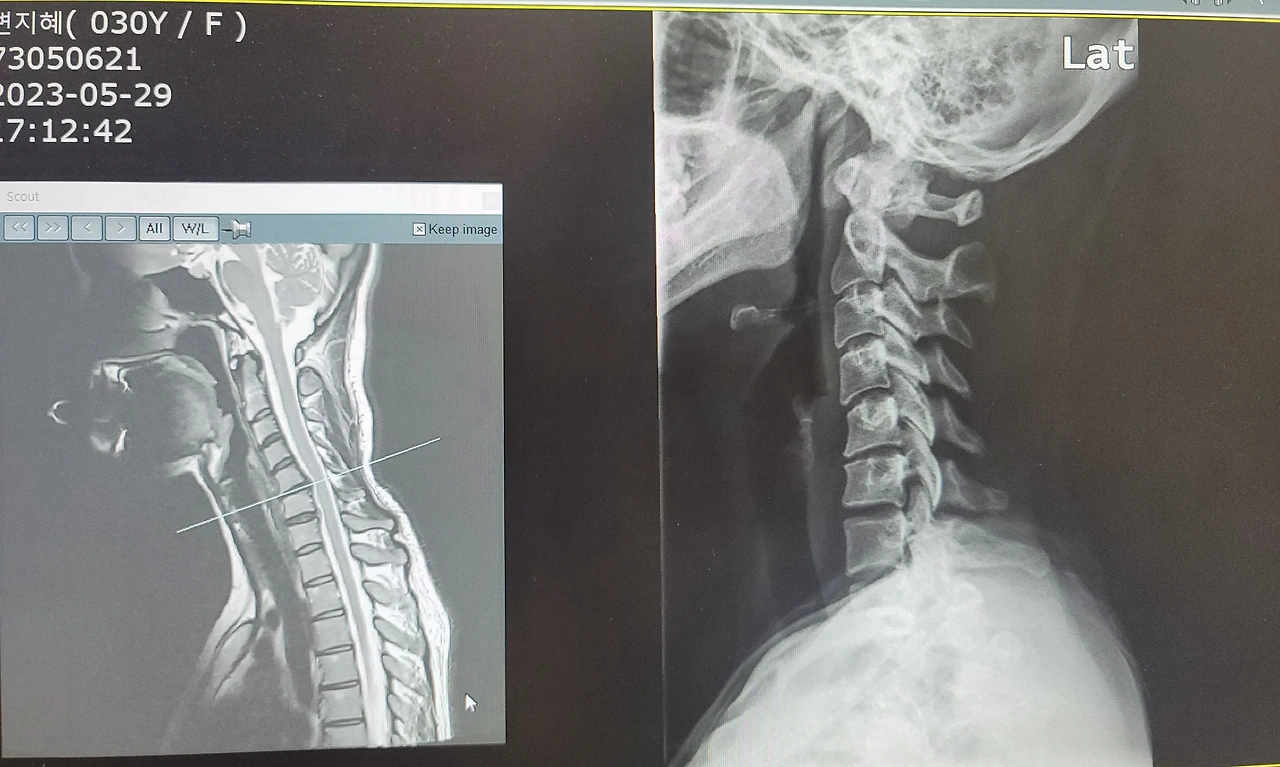

목 디스크가 하나 더 튀어나오셨네요.

하루 입원해서 MRI까지 찍어본 결과. 목디스크가 총 2개가 튀어나와 나를 아프게 하고 있었다. 평소 운동을 열심히 해서 괜찮아졌을 거라고 믿음들이 공중분해 되는 날이었다. 옆에 부축해 주는 사람 없이. 혼자서 병원에 가서 입원수속을 했다. 입원실에 앉아있다가, 디스크 염증을 가라앉히는 스테로이드 주사치료를 맞았다. 그리고는 혼자 멍하게 입원 침대에 누워있었다.

백 년 허리라는 책을 쓰신 작가. 교수님께서 '백 년 목'이라는 책도 내셨다고 친구에게 전해 들었다. 시중에는 지금 절판되어서 없어서 놀랬다. 곧바로 주말에 도서관으로 달려갔다. 목을 백 년 동안 튼튼하게 만들 방법을 얻기 위해 책장을 열심히 넘겼다. 그리고는 한 가지만 알아가면 되는 걸 알았다. 날개뼈를 붙이며 가슴은 들고 고개를 뒤로 젖히는 자세를 정말 꾸준히 하면 좋아진다는 것이다. MRI까지 변화과정이 적혀 있으니, 신빙성이 있어서 믿어보기로 했다. 그래서 요즘은 이 자세를 수시로 하는 중이다.